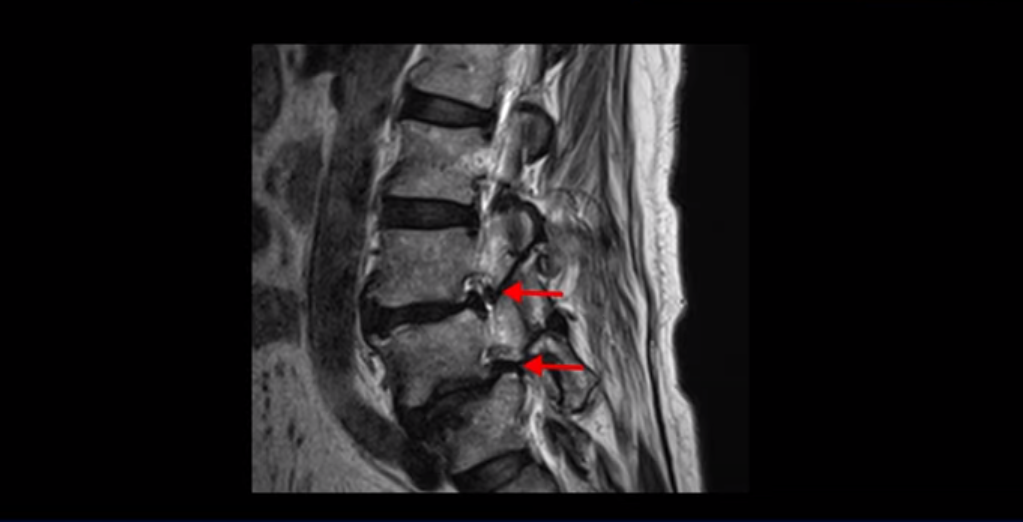

실제 저희 치료후기에 나오는 환자분들의 사례를 들어 설명해드리겠습니다. 이분은 전방전위가 2단계로 매우 심하고,

신경 구멍도 두 마디가 좁아져 있습니다.

전방전위와 협착이 다 심하니까 대학병원에서 나사 6개를 박는 유합술을 권유 받으셨는데요. 그런데 이분이 처음 아프게 된 건 작년 10월인데, 이분이 만약 아프기 전인 작년 초에 MRI를 찍었다면 지금의 MRI와 많이 다를까요? 아닙니다. 거의 차이가 없을 겁니다. 이미 척추 뼈는 많이 밀려나가 있고 신경 구멍은 똑같이 좁아진 상태였을 겁니다. 그 상태로도 전혀 안 아프게 아주 오랫동안 사신 겁니다. 그러다가 작년 10월에 무리한 일과 운동 때문에 허리 근육에 문제가 생기면서 신경이 눌리기 시작한 겁니다. 만일 아프지 않을 때 MRI를 찍고 척추 뼈가 밀려나가고 신경이 눌렸으니까 나사 박는 수술을 하자고 하면, 수술을 받을 사람이 있을까요?